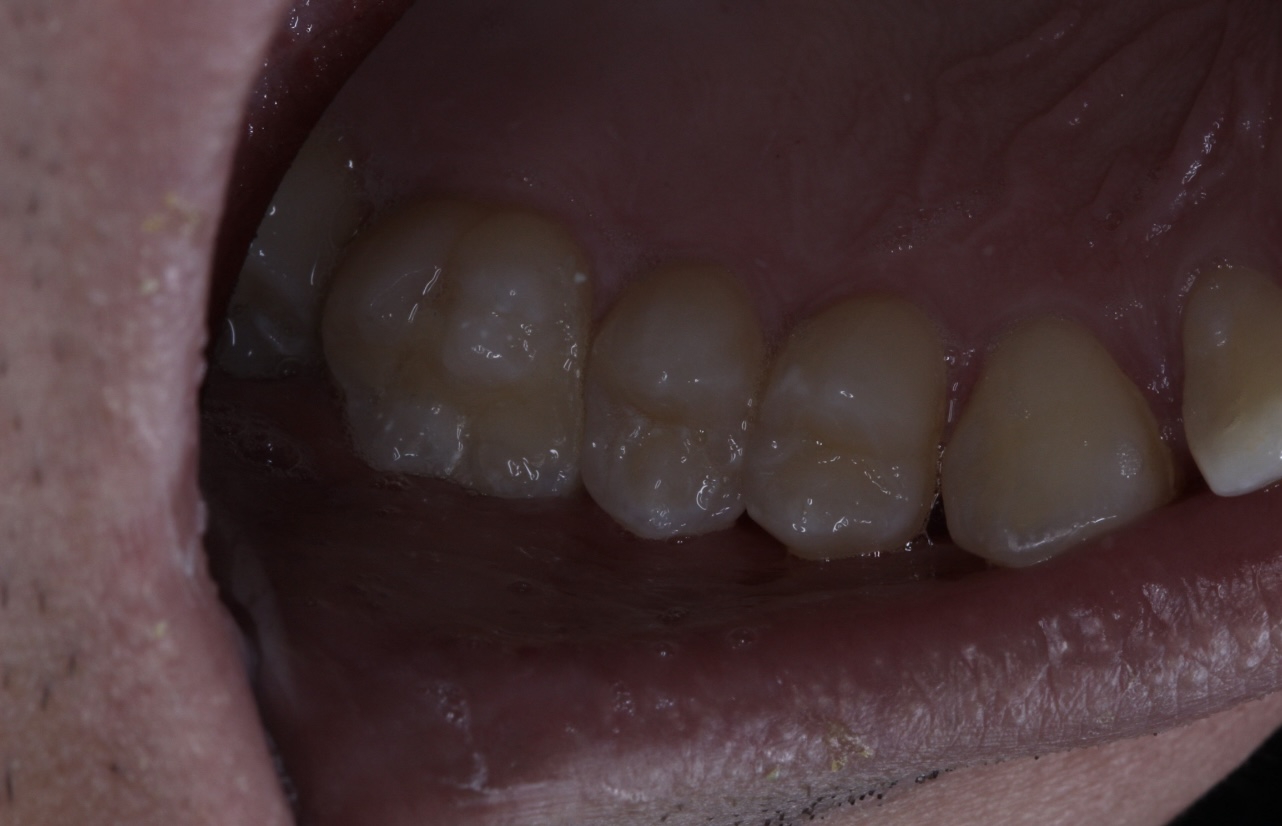

>>1634947

>Как профиль лица меняется после удаления восьмерок